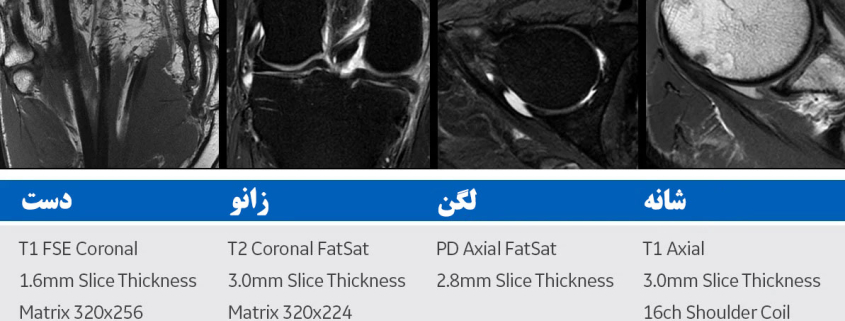

نحوهی انجام ام آر آی عضلانی اسکلتی (Musculoskeletal MRI)

ام آر آی عضلانی اسکلتی شامل دراز کشیدن روی تختی است که به داخل دستگاهی بزرگ و لولهایشکل حرکت میکند.

این دستگاه با استفاده از میدان مغناطیسی قوی و امواج رادیویی، تصاویری دقیق از عضلات، استخوانها و مفاصل بدن ایجاد میکند.

- روی تخت متحرک دراز میکشید و تکنولوژیست MRI کویل مخصوصی را در اطراف ناحیهای که باید تصویربرداری شود قرار میدهد.